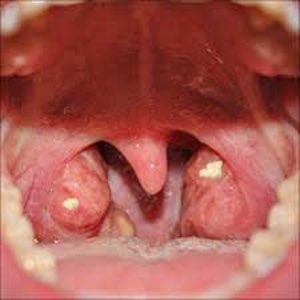

وهي اللوزتين

معظم الناس قد لا يفكرون ان اللوزتين قد تكون سبباً لرائحة الفم؟!

قد يترسب الكالسيوم في حالة تسمى حصوات اللوزتين

وهذه تسبب رائحة الفم الكريهة

◼️ بعض الناس قد تتكون لدهم حصوات اللوز بشكل اسبوعي

◼️و غالبا هؤلاء الأشخاص تكون لديهم فتحات أو نتواءات في اللوزتين، تجعلهم اكثر عرضة لتكونها